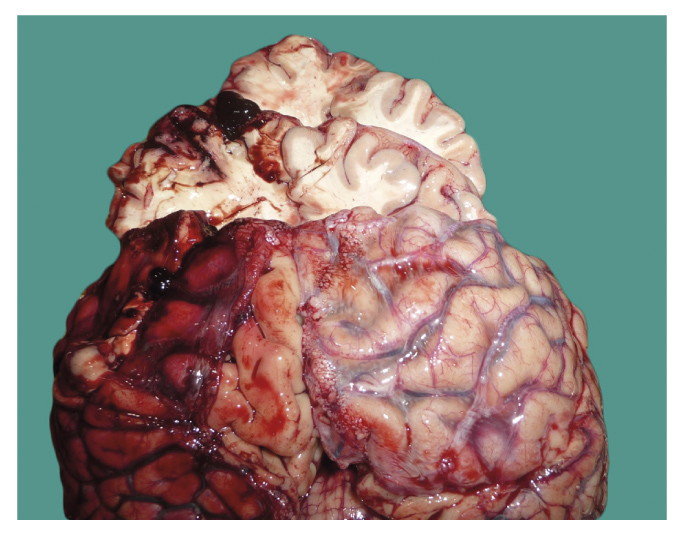

Извилины головного мозга уплощены, борозды между ними резко сужены. Под мягкой мозговой оболочкой практически на всём протяжении выпуклой поверхности левого полушария обнаружено очагово-диффузное субарахноидальное кровоизлияние. Здесь же на разрезах в коре и подлежащем белом веществе левого полушария большого мозга местами прослеживаются множественные мелкоточечные и полосовидные кровоизлияния с геморрагическим пропитыванием окружающих тканей (рис. 2).

Рис. 2. Субарахноидальное кровоизлияние слева; в коре и подлежащем белом веществе головного мозга на разрезах прослеживаются мелкоточечные и полосовидные кровоизлияния (зона противоудара).

Fig. 2. Subarachnoid hemorrhage on the left sections in the cortex and the underlying white matter of the brain, small punctate and stripe hemorrhages are traced (the counter-impact zone).